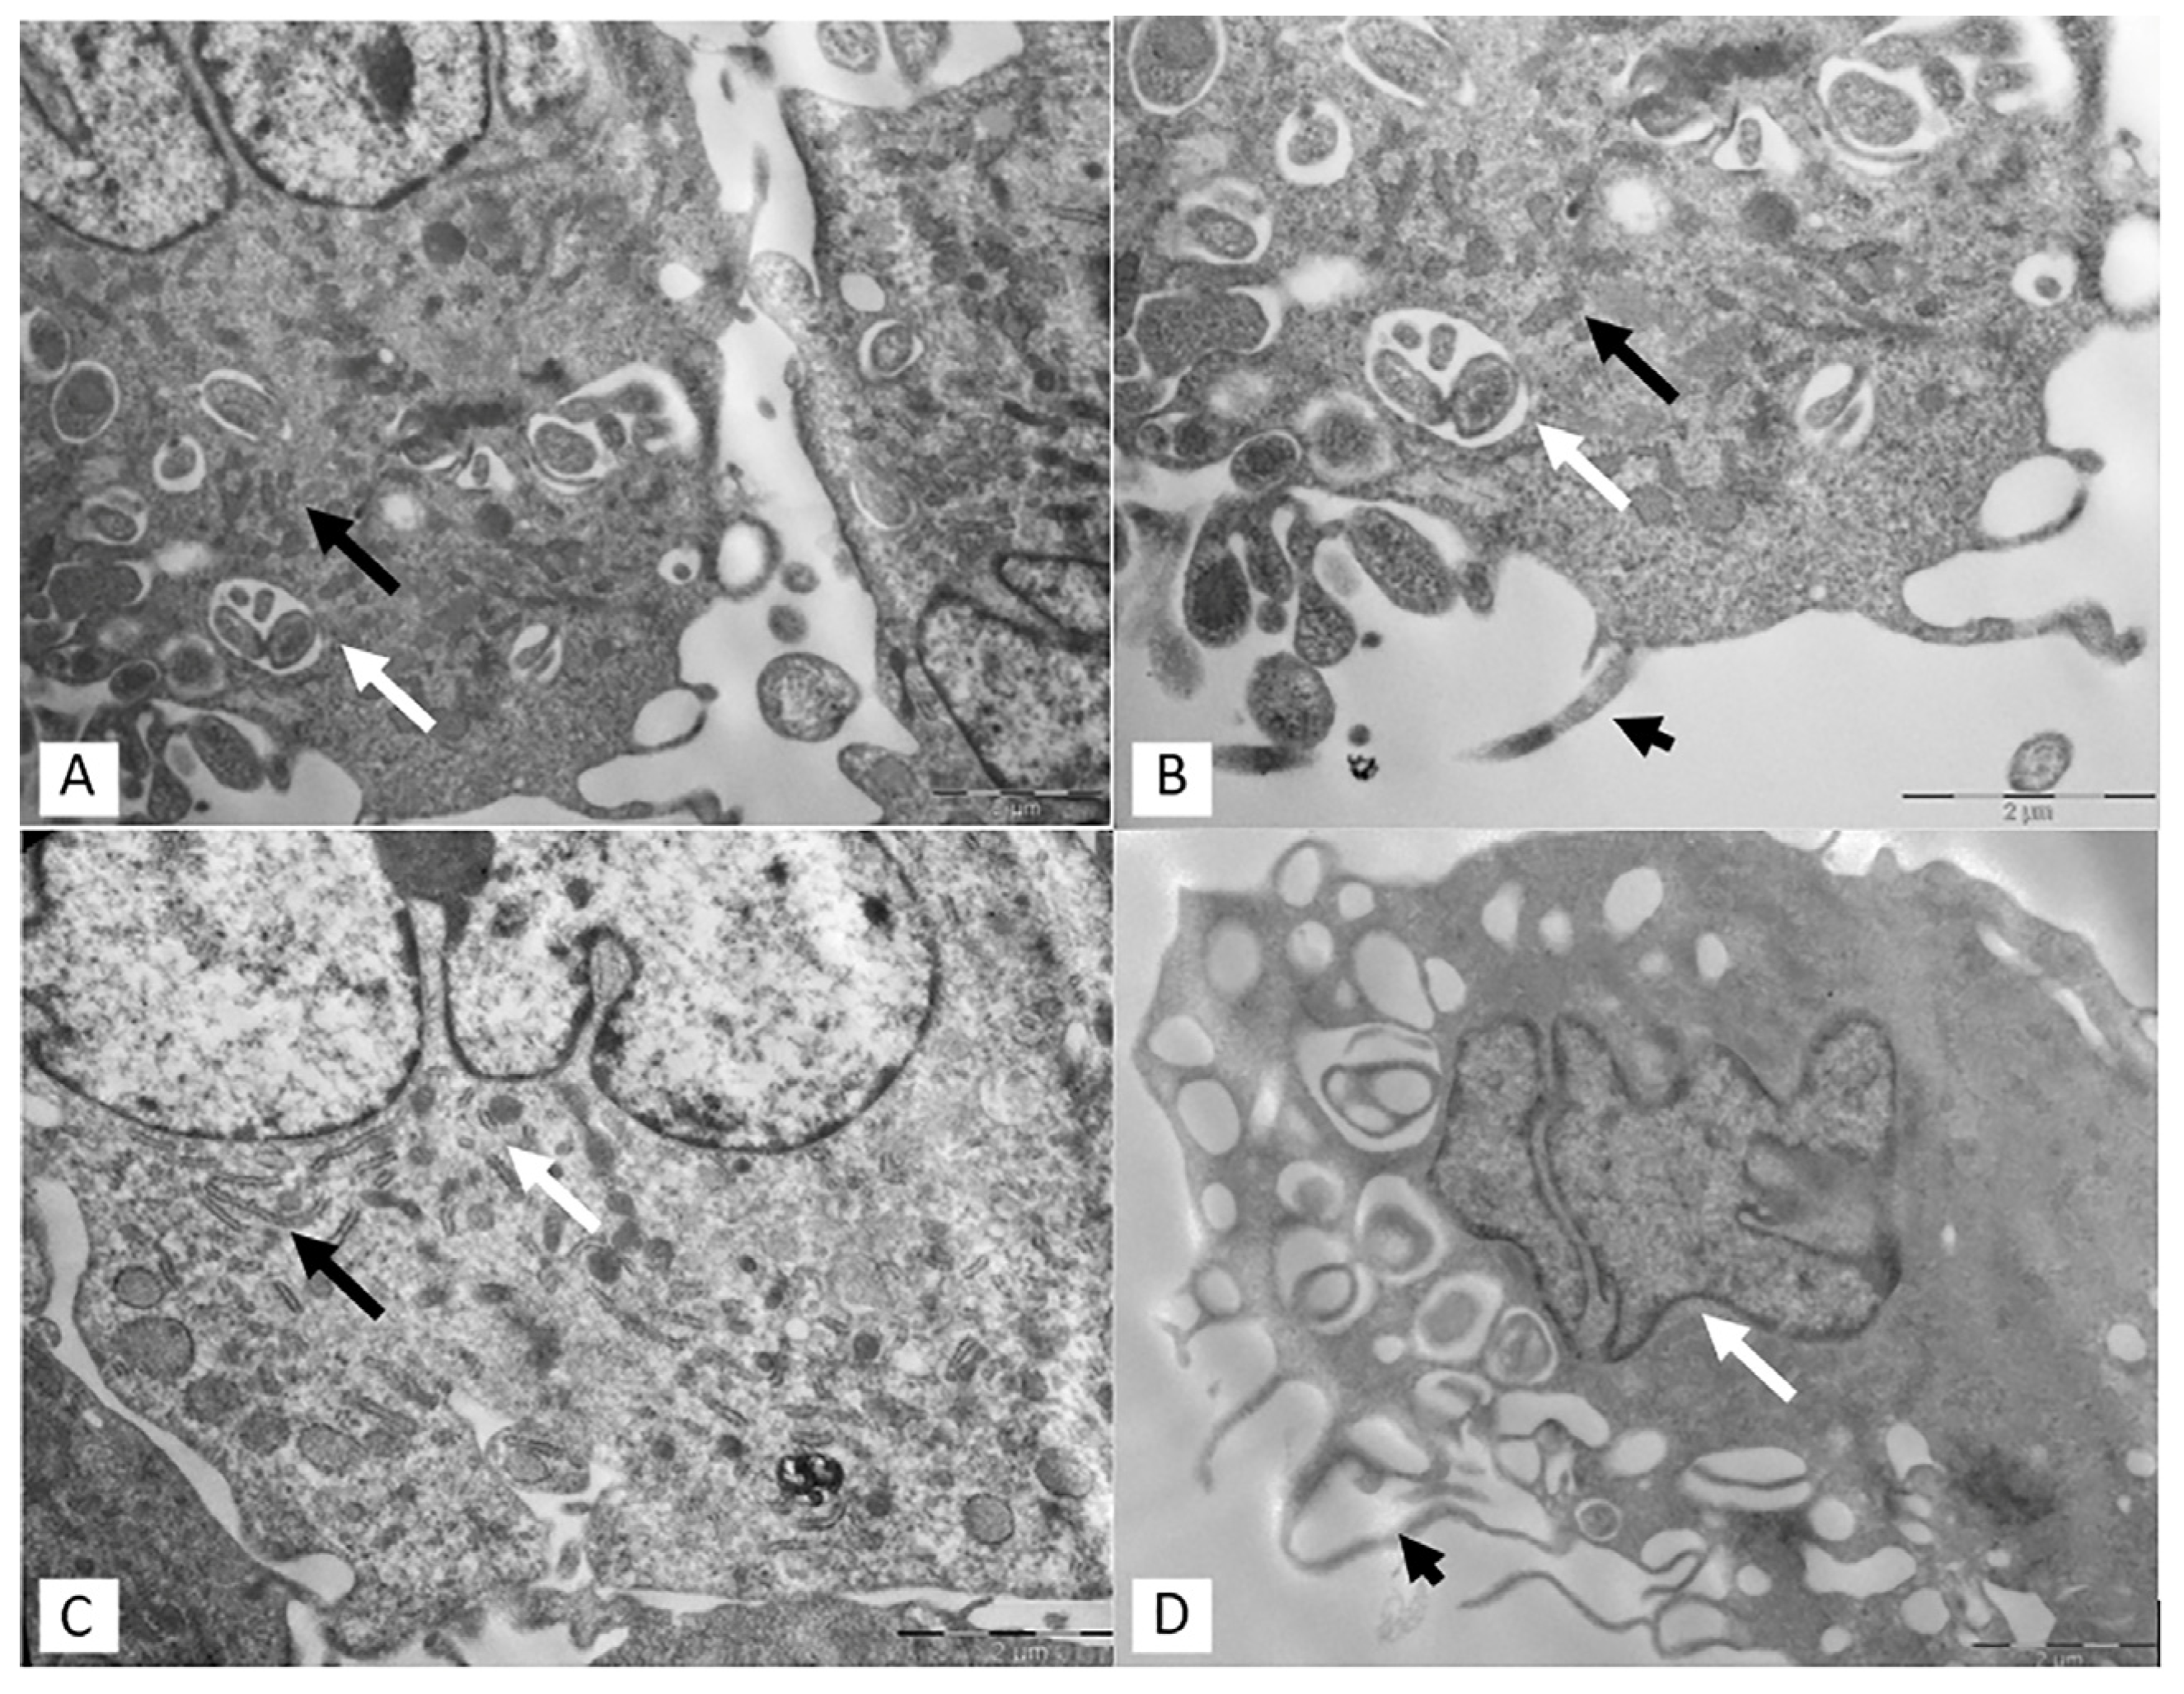

3.2. Transmission Electron Microscopy (TEM)